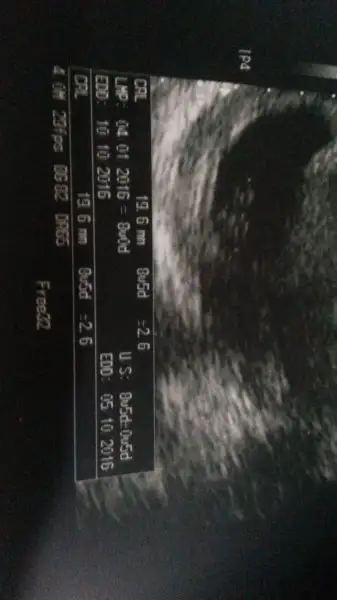

1456324577679-37548056.webp arkadaşlar yorumlar misiniz erkek mi kiz m​

Usg karındansa kız gibi,vajinalsa erkek gibi cnm

Karından usg.Canım ilk sayfada sağda durarsa kız yazıyordu sanki ama teşekkür ederim

Senin bebek sola yakin,vajinal usg ile karından usg farklı.o yüzden seninki karındanmis bu teoriye erkek oluyor cnm.